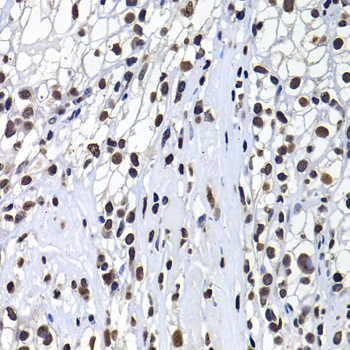

Immunohistochemistry of paraffin-embedded human kidney cancer using mH2A1 antibody.